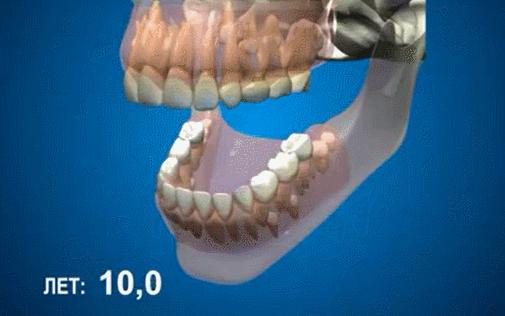

① 宝宝在6-7岁的时候,开始长出要伴随自己一生的牙齿,中切牙。这个时候宝宝的第一磨牙也在“暗中发力”。

③ 宝宝在10-12岁的时候,双尖牙开始“破土而出”,也就是我们常说的小*牙虎**。